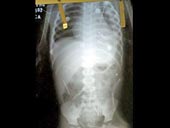

Tuần trước, một bà mẹ bế con trai 2 tuổi đến bệnh viện ở thành phố Ibotirama, Đông Bắc Brazil vì bé luôn miệng kêu đau. 3 ngày sau, các bác sĩ quyết định chuyển bé sang bệnh viện lớn hơn sau khi nhìn phim X-quang phát hiện có đến 50 chiếc kim, dài khoảng 5 cm, nằm ngang dọc trong khắp cơ thể bé (ảnh). Người mẹ không biết làm thế nào số kim này lại ở trong người bé, còn ông bố thì cho rằng con mình là nạn nhân của một loại tà thuật. Trong khi đó, cảnh sát bắt giữ bố dượng trước đây của bé. Gã này thú nhận đã ghim số kim đó vào cơ thể đứa trẻ với sự giúp đỡ của 2 phụ nữ.

Các bác sĩ cho biết sức khỏe của em bé khá hơn nhiều so với lúc mới nhập viện. Họ sẽ sớm lấy hết số kim khâu ra khỏi cơ thể bé nhưng với những chiếc nằm trong phổi, họ phải chờ cho đến khi chức năng hô hấp của bé được cải thiện tốt hơn.